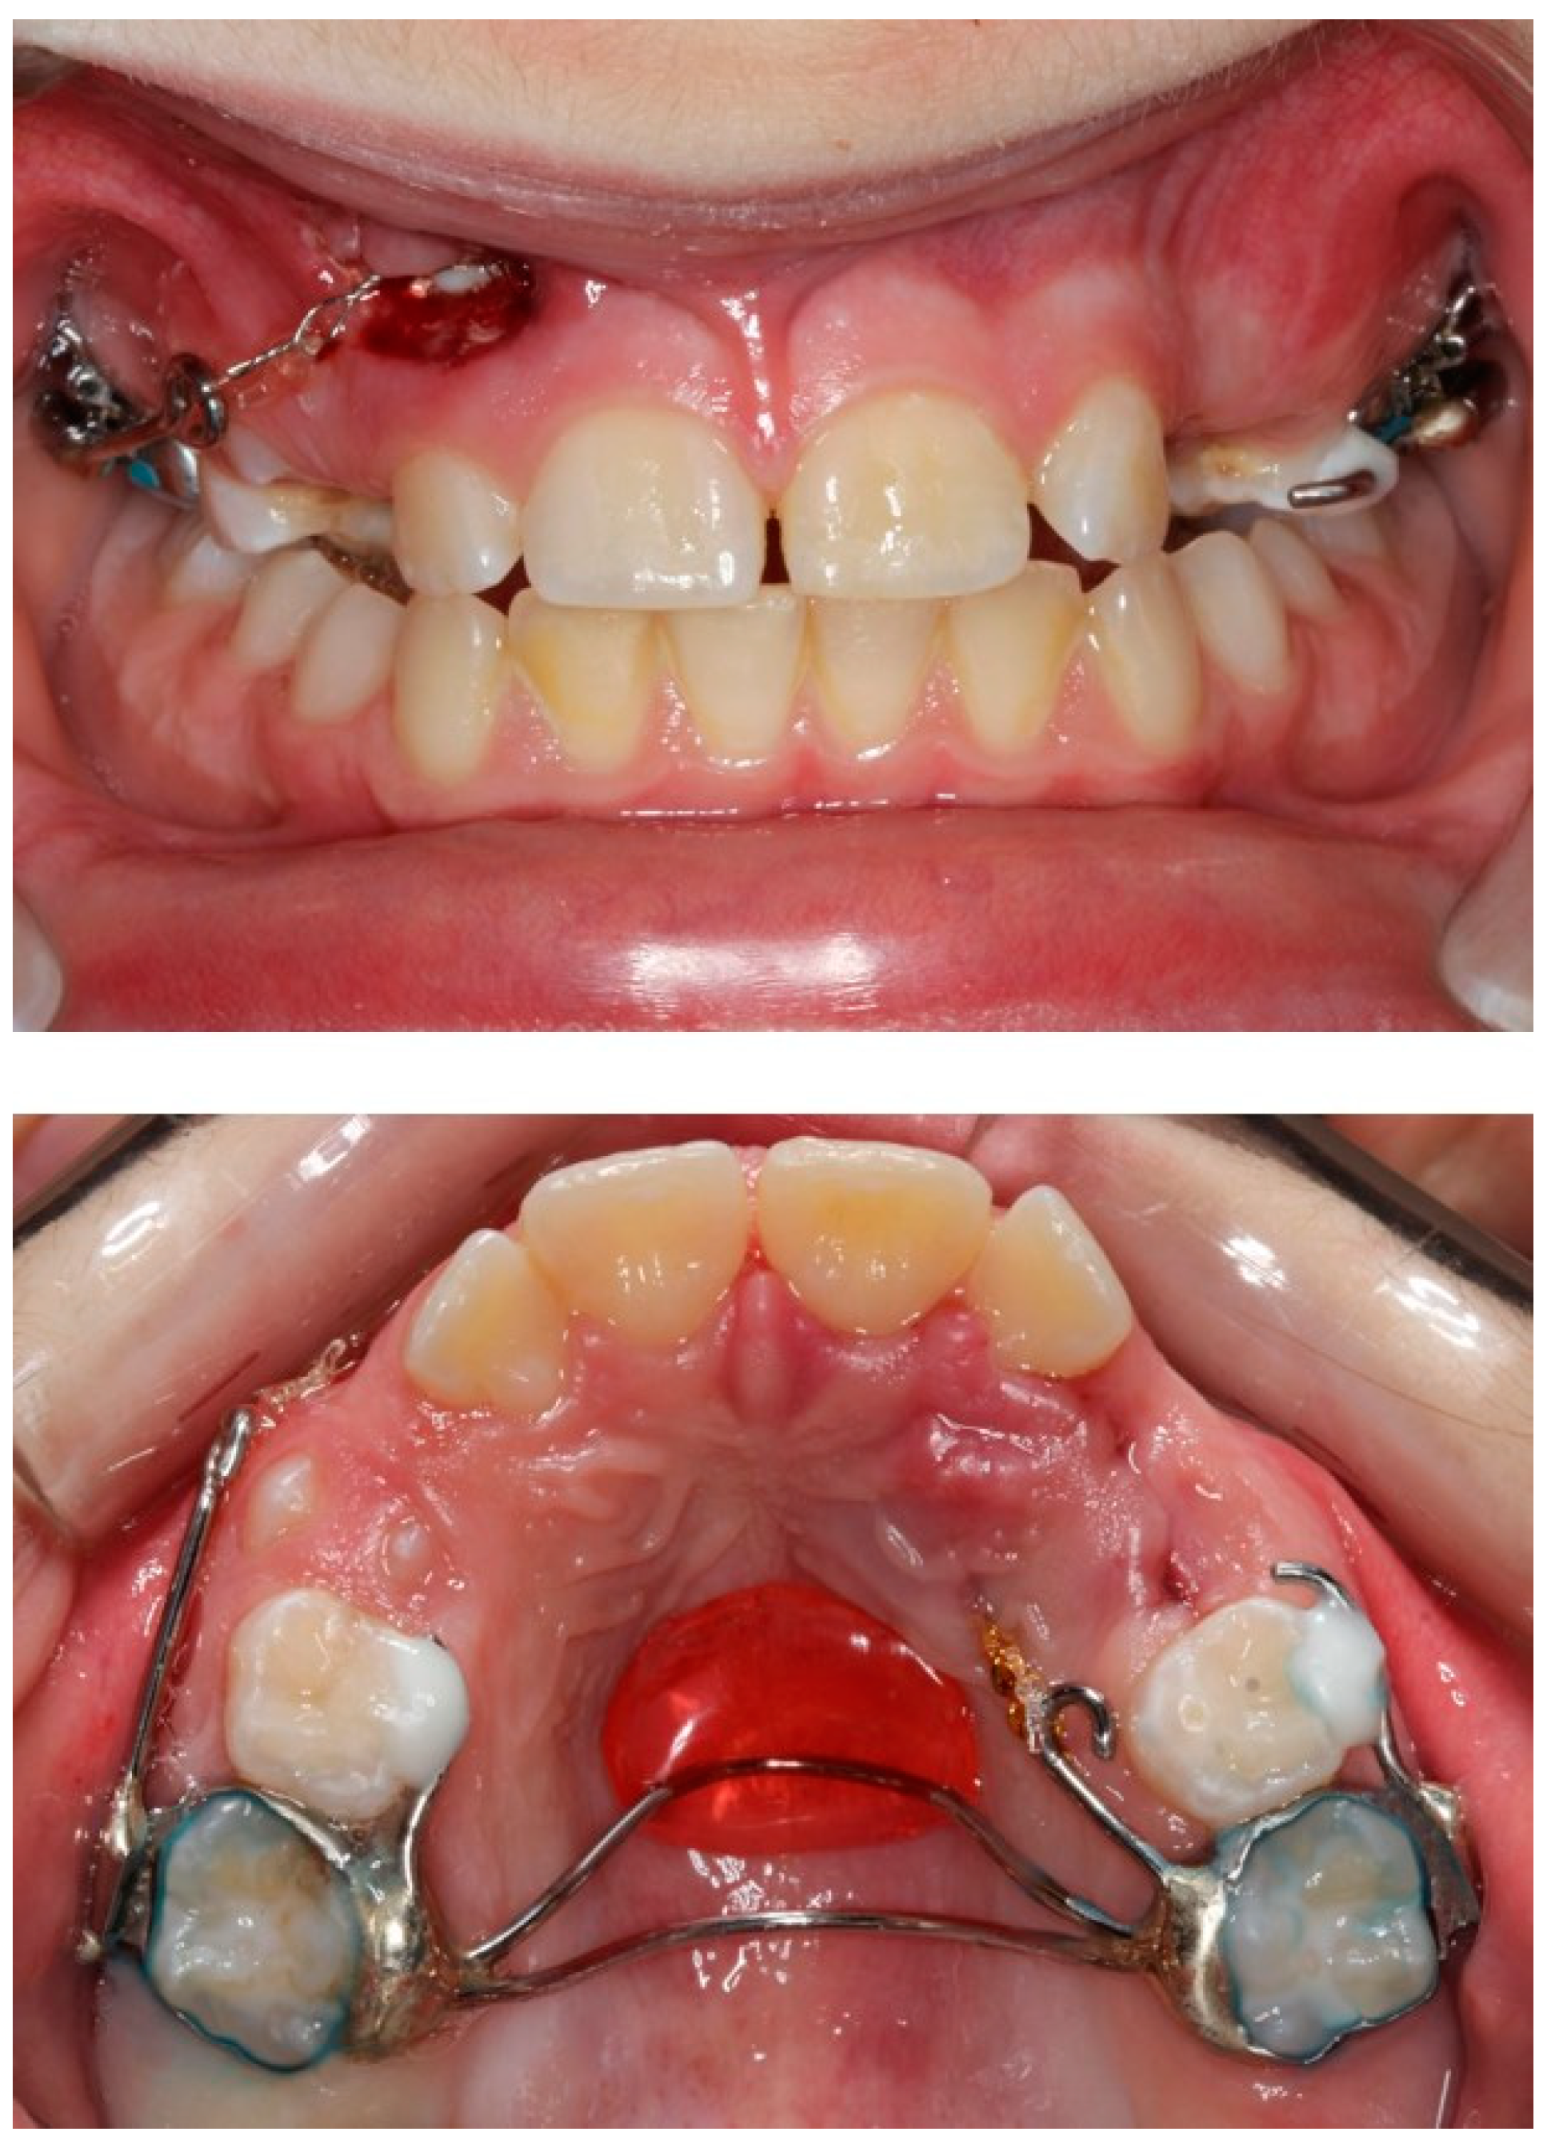

2.4. Treatment Results

2.5. Retention